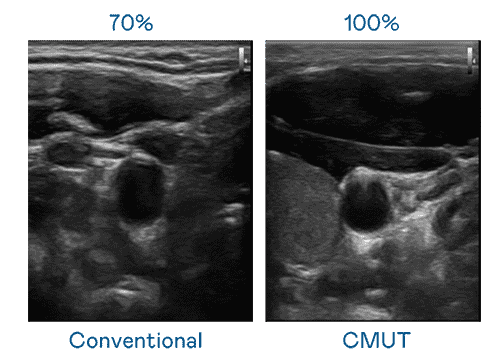

CMUT 技术是一种用电容式微机电元件来产生超音波讯号的技术。。与传统 PZT 压电式技术相比,,,,CMUT 频宽增加 30%,,,,更宽频的超音波讯号让影像解析度大幅提升,,,,是实现高影像品质医疗超音波扫描、、促进精准医疗发展的关键技术。。。

超音波影像的解析度高低,,,,首先取决于探头能发出的讯号频宽。。。开云电子 CMUT 可提供高清晰的超音波讯号,,提供高频宽、、、、高灵敏度、、影像纹理细节更高的超音波影像,,协助医护人员缩短影像判读时间及利用精准的医疗影像进行诊断。。